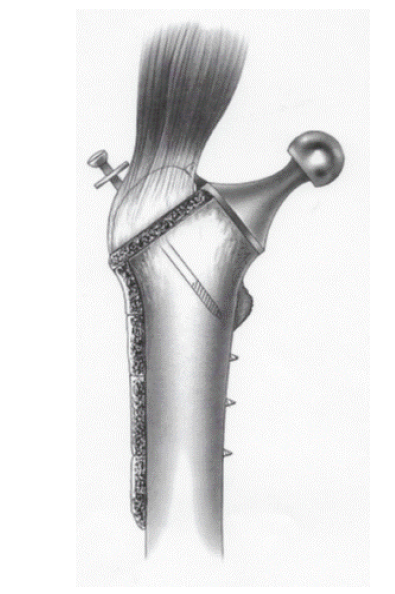

Figure 1 shows as the first femoral component was in Chrome Cobalt alloy. (Vitallium). The second is in Titanium. The femoral component is screwed on the lateral femoral shaft. The screw diameter is 5 mms (c) to fix the plate on the femoral shaft and 7 mms (a) to maintain the greater trochanter. Two teeths (b) prevent gluteus medius muscular action. The hole’s plate and screw’s design are according to the Meyrues and Cazenave’s experimental work [8].

Figure 1. Female implant with external cortical support